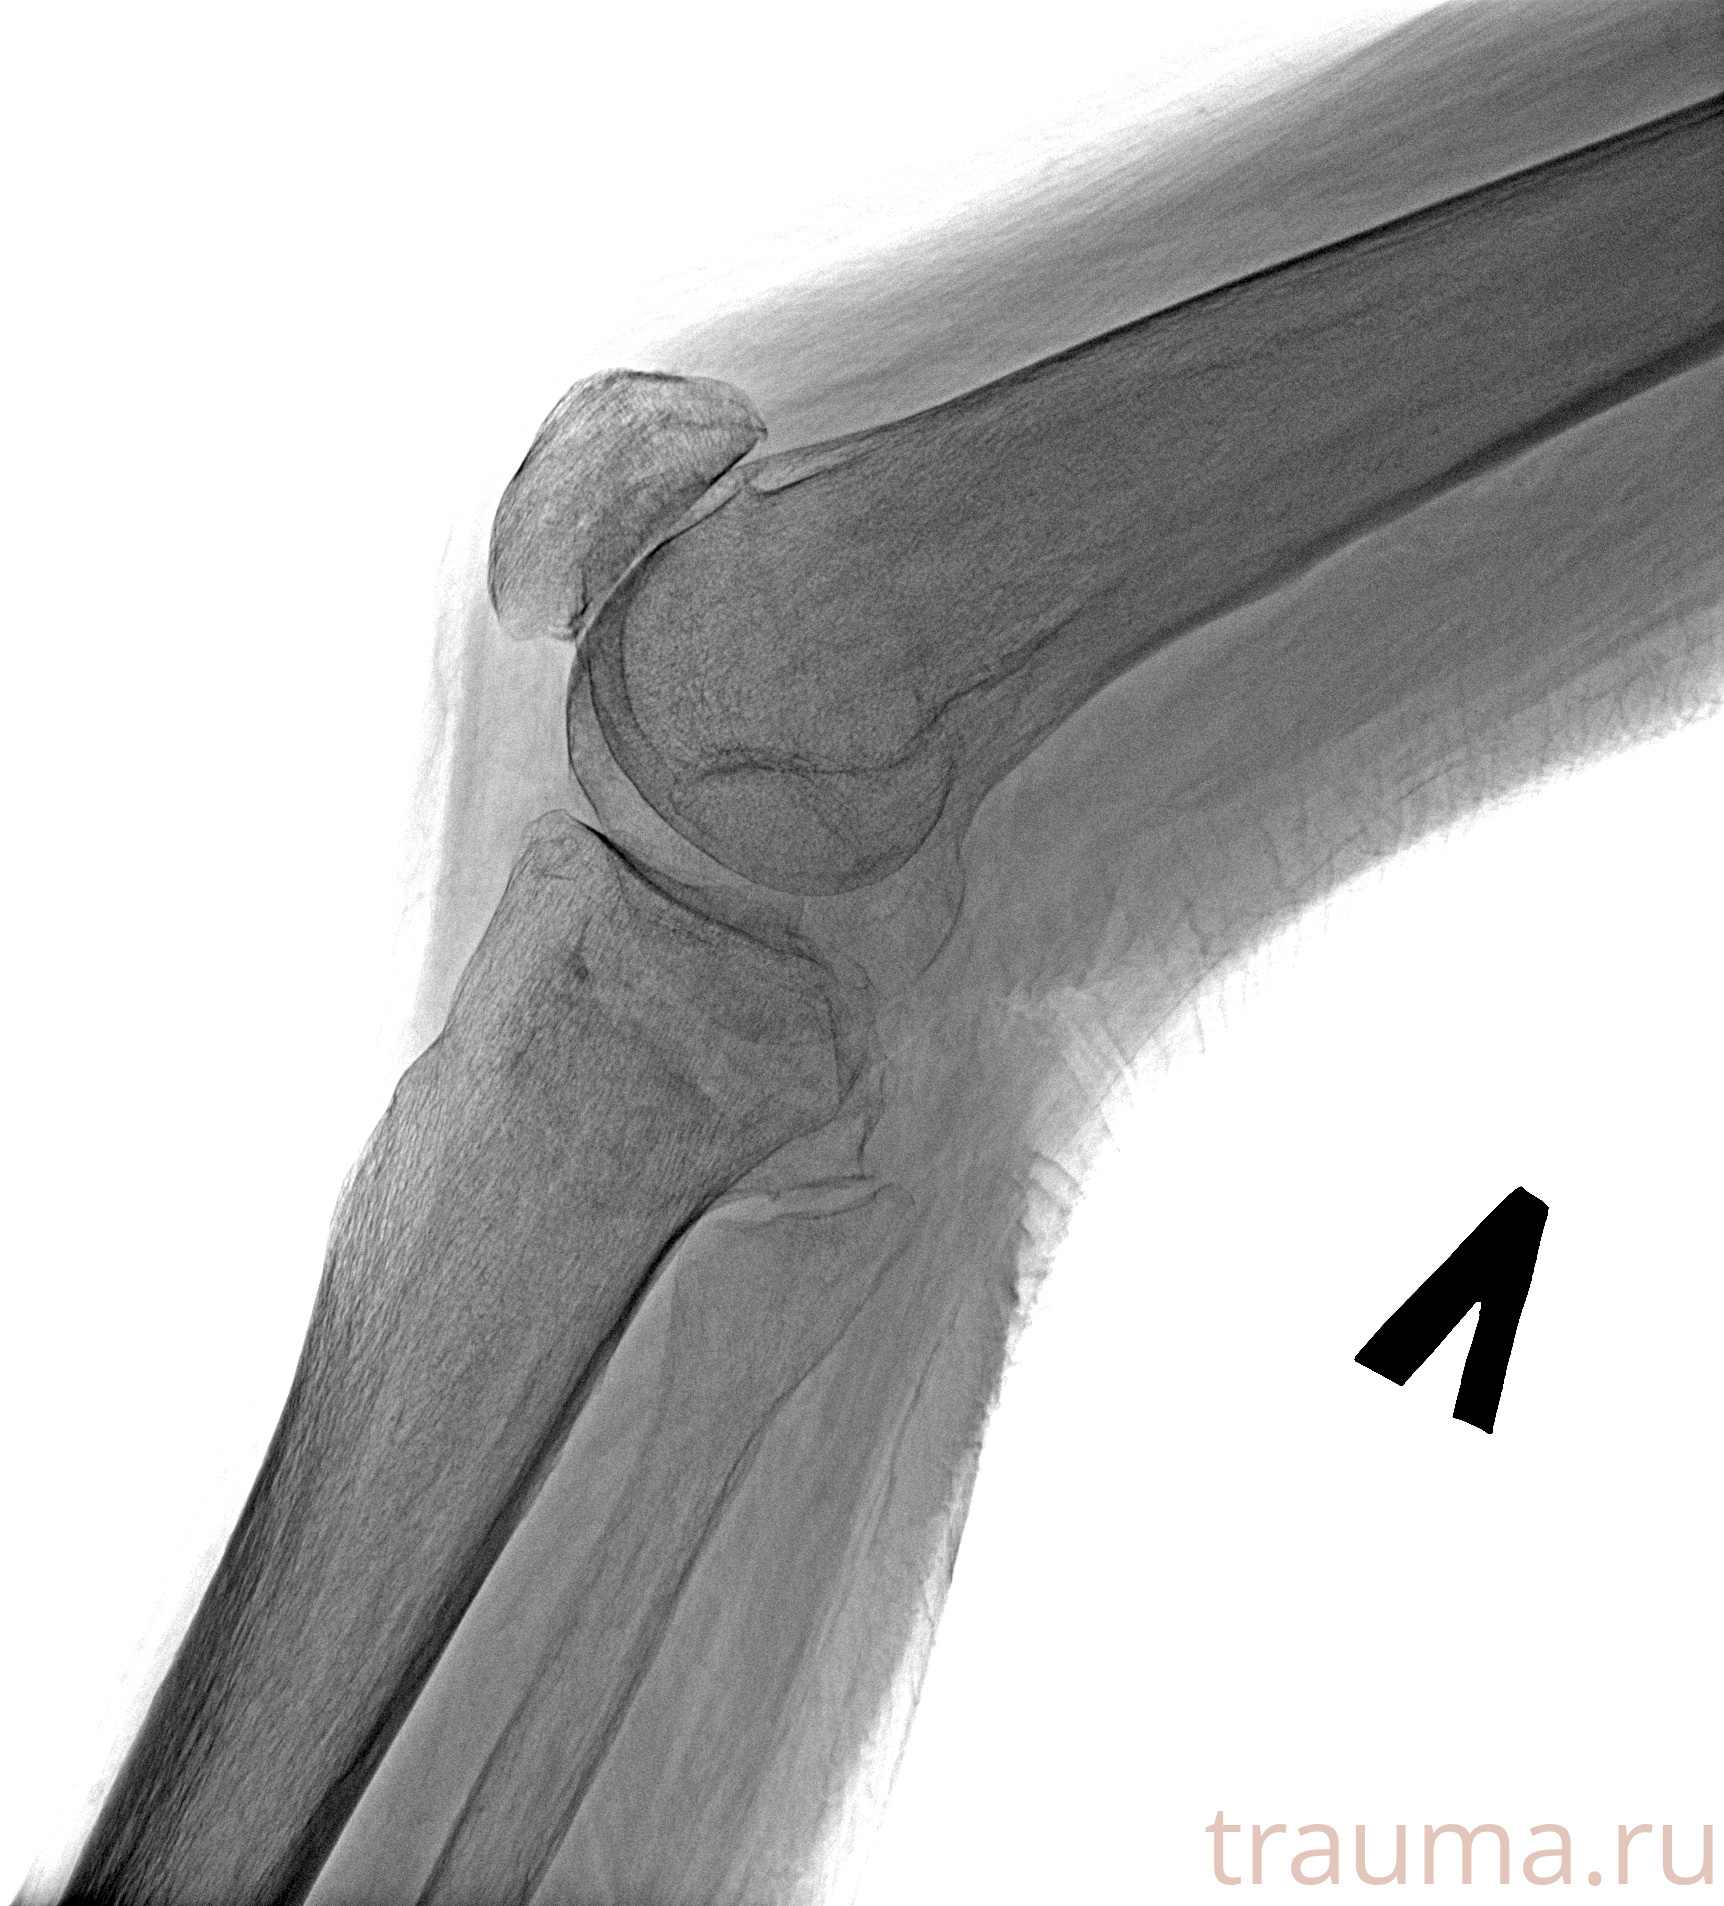

Рентгенограммы

Рентген на дому: по вашему адресу приезжает врач-рентгенолог, травматолог-ортопед с мобильным рентгеновским аппаратом, проводит диагностику травмы или заболевания, делает необходимые рентгенограммы, дает рекомендации по дальнейшему лечению. Получить качественные снимки в домашних условиях возможно благодаря уникальной методике, разработанной МосРентген Центром для института  Склифосовского